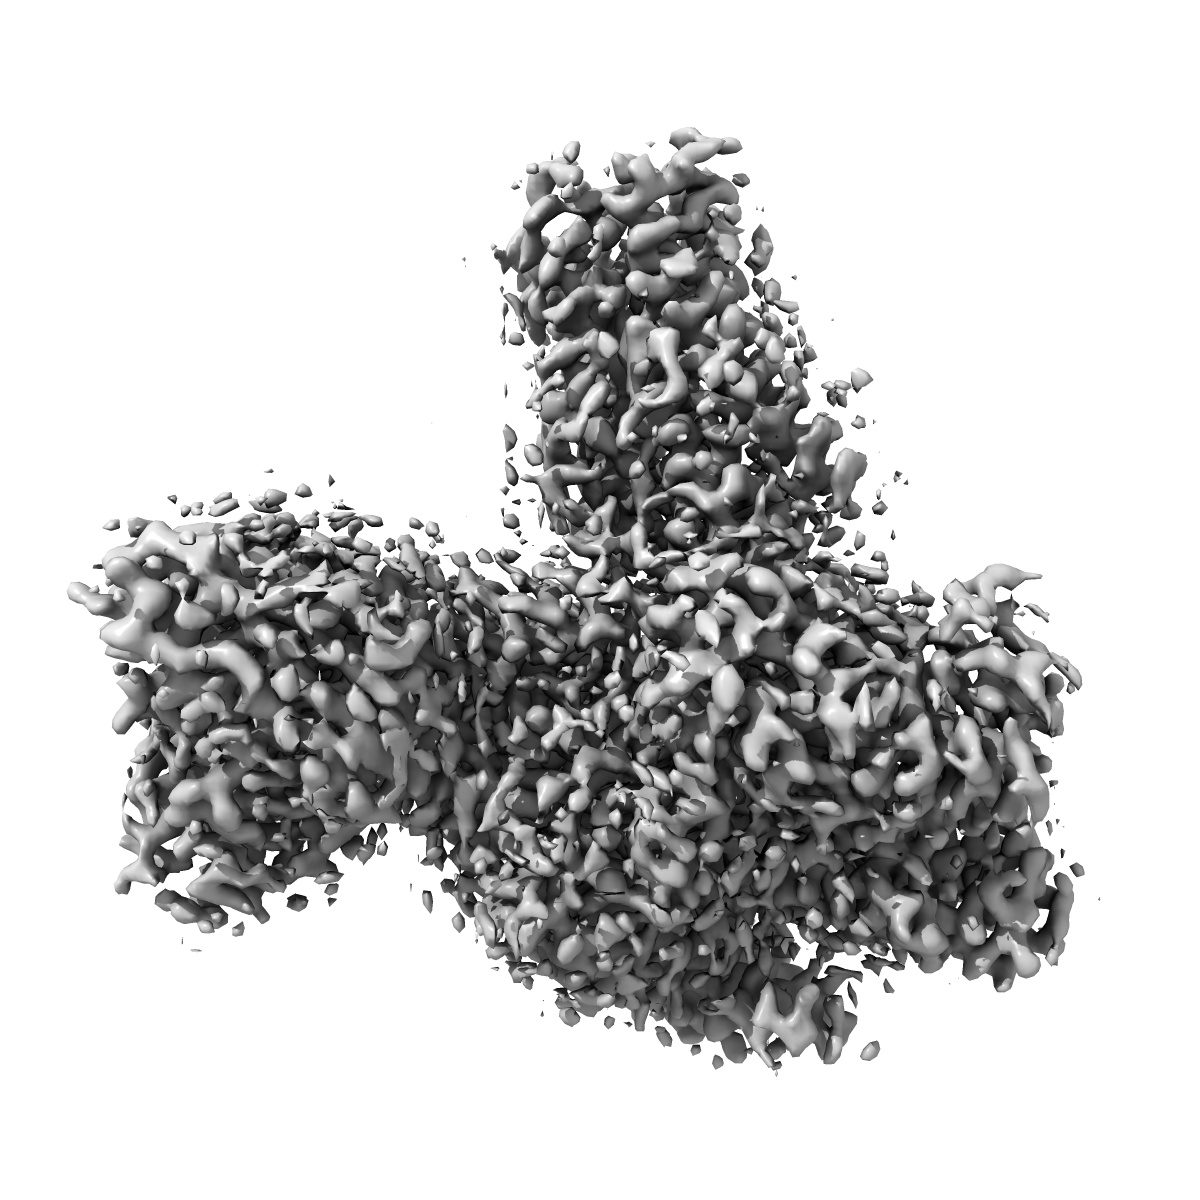

Cryo-EM structure of the imetit-bound histamine H4 receptor and Gq complex

Sample: Imetit bound histamine h4 receptor in complex with Gq

Fitted models: 7yfd

Structural insights into the agonists binding and receptor selectivity of human histamine H 4 receptor.

Im D , Kishikawa JI , Shiimura Y, Hisano H, Ito A, Fujita-Fujiharu Y , Sugita Y , Noda T, Kato T , Asada H , Iwata S

(2023) Nat Commun , 14 , 6538 - 6538